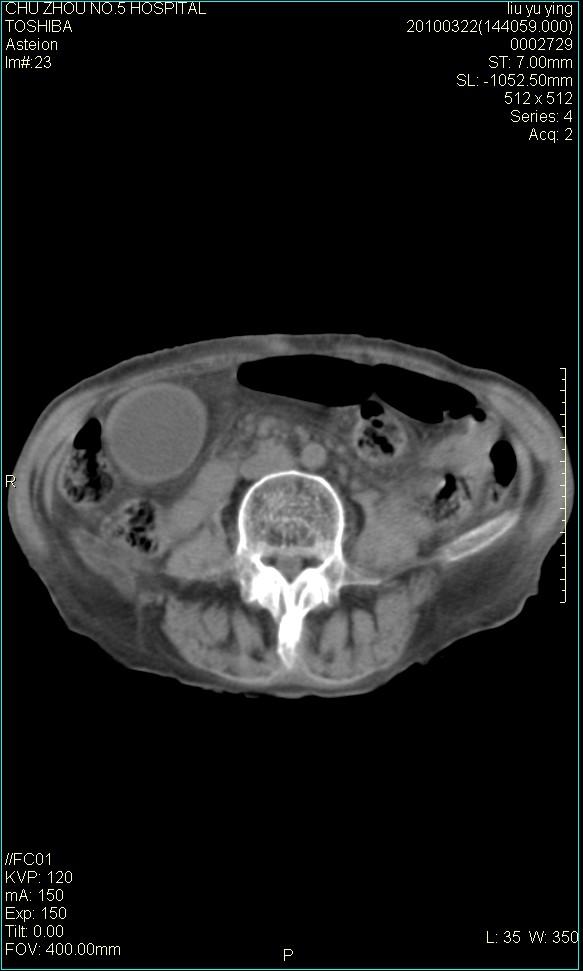

以下是引用科室第一人在2010-3-23 6:50:00的发言:[br]胆总管下段梗阻,多为肿瘤性病变,巨形胆囊,胆囊炎胆囊窝积液。[br]双侧胸腔积液,右降

以下是引用随光逐影在2010-3-23 8:12:00的发言:[br]1)胆系低位梗阻(肝内外胆管扩张,胆囊增大),原因待查。2)胆囊炎。3)双侧少量胸腔积液。4)降主动脉迂曲。